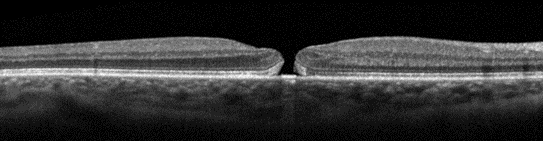

Macular Hole

Macular hole is a defect in the retina at the macula. Due to its location at the macula, the portion of the retina responsible for central vision, patients can present with metamorphopsia (central vision distortion) or loss of central vision. While the clinical features of macular hole are in line with the symptoms endorsed by this patient, the examination and imaging findings on OCT are inconsistent with macular hole. See the example below of macular hole on OCT.